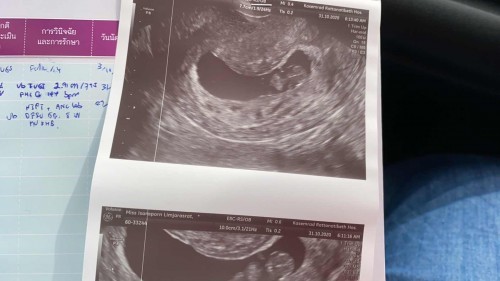

ท้อง 12week+ หมอตรวจไม่เจอการเต้นของหัวใจ ซาวน์ผ่านช่องคลอดก็ไม่เจอ เปลี่ยน 2 โรงพยาบาล เกษมราษฏร์อินเตอร์ กับ สมิติเวชธน น้องขนาดเท่าเด็ก 8 week ไม่เคยเลือดออก ไม่มีปวดท้องหนักๆ มีแค่หน่วงนิดหน่อย จนตอนนี้ก็ยังไม่เป็นอะไร แต่หมอยืนยัน 90% ว่าน้องไม่อยู่แล้ว มีใครเคยเจอเคสนี้ไหมคะ#ขอบคุณสำหรับคำตอบค่ะ #ท้องแรกคะ